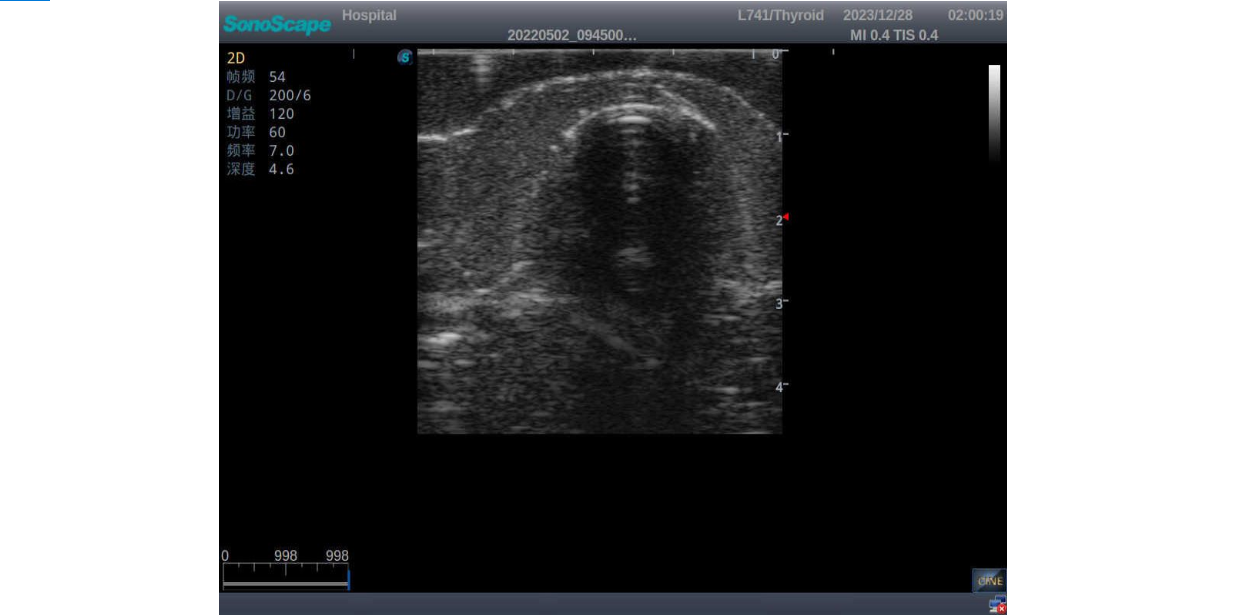

3) It comes with four (4) thyroid modules and can show five (5) ultrasonic images: normal thyroid, thyroid adenoma, thyroid cancer, nodular goiter, thyroid cyst

Thyroid cancer with irregular mass, unclear border, uneven internal echo or calcification strong echoes